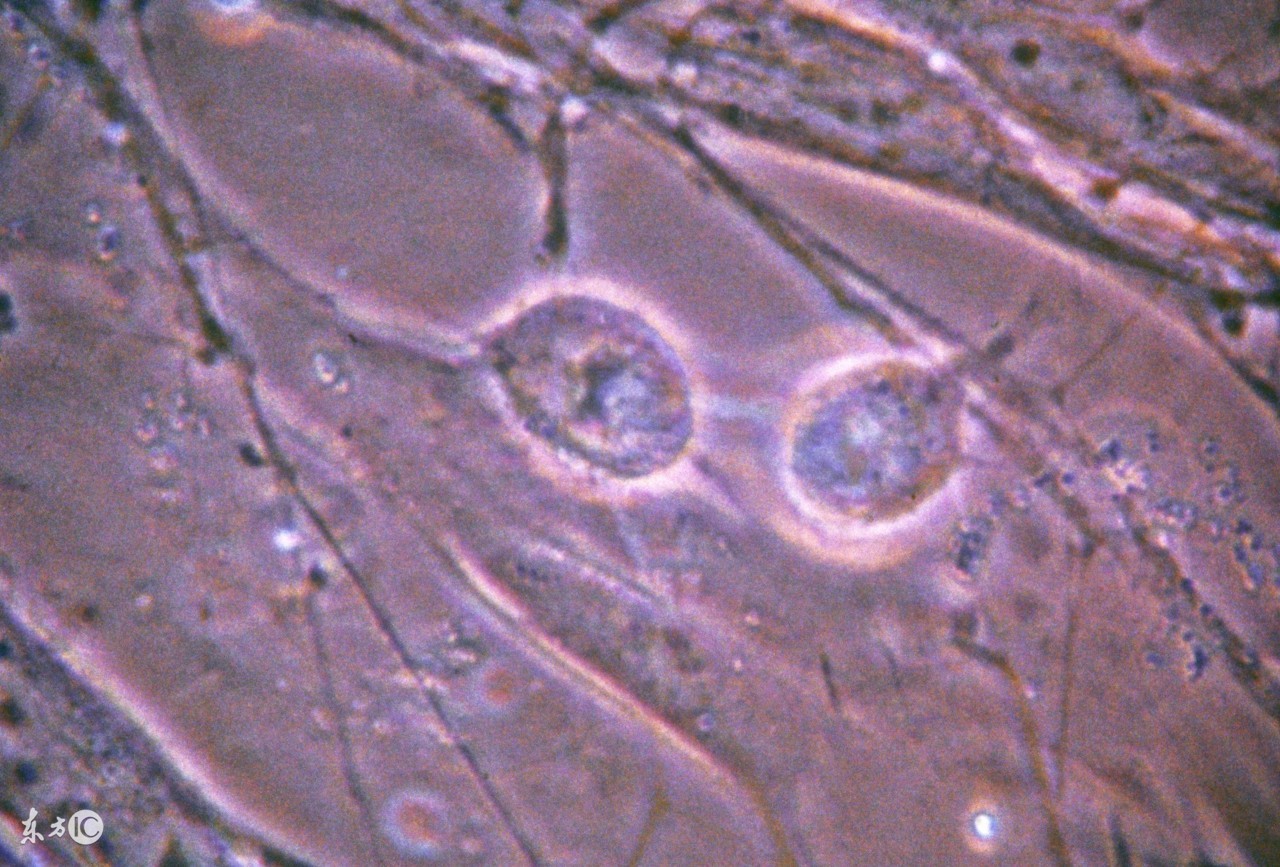

正常生育年龄的妇女卵巢每月只排出一个卵子。原始卵泡发育到成熟,形成成熟卵泡并排卵,约需14天左右,其间经历了一系列复杂的生理生化反应,在这个过程中卵泡中的特殊的细胞分泌雄性激素和雌性激素,雌性激素调节子宫内膜的周期性变化,就形成了月经周期。